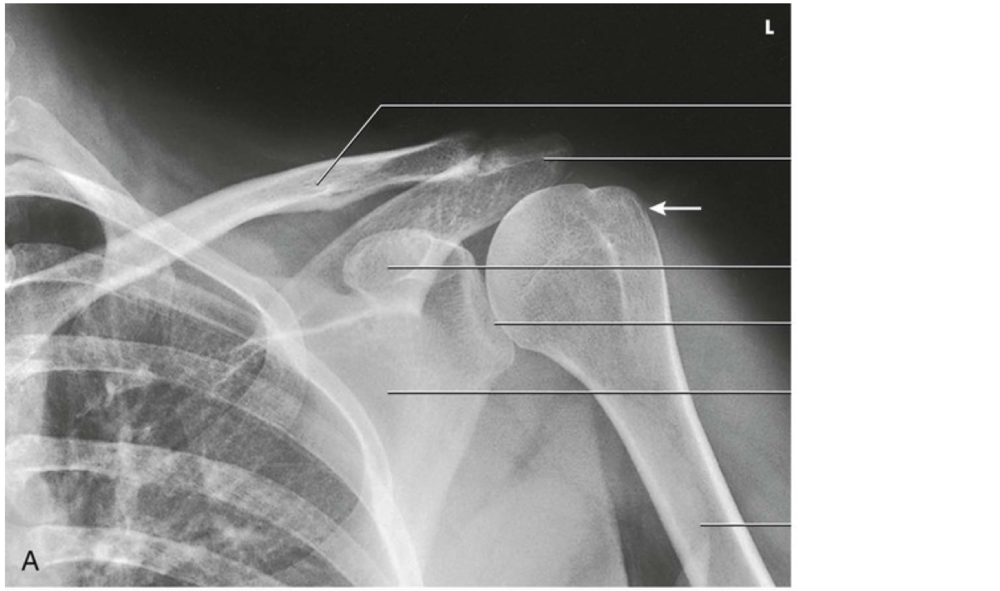

Question 11

Question

Label the image

Image:

b2b11331-4770-43e9-a0ed-661e02d896b7 (image/png)

Answer

unaffected clavicle

scapula (superior border)

sternum

clavicle

acromion process

humeral head

scapula (lateral border)

proximal humerus